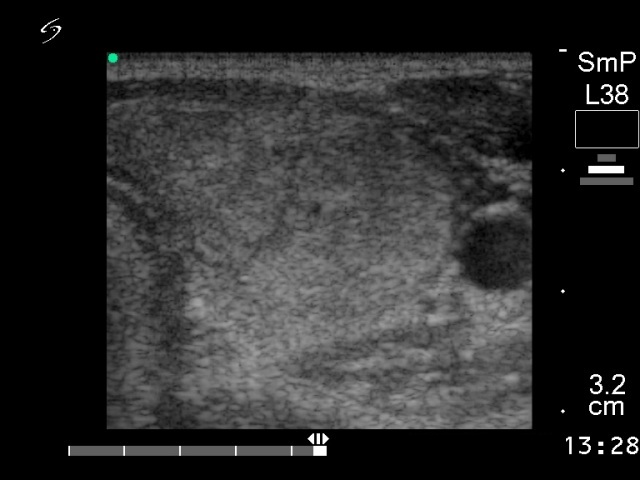

Ethanol sclerotherapy: non-toxic solid nodules - Case 5

First session of therapy

(ultrasonographic picture 1)

Left lobe,horizontal scan. There is a large echonormal nodule.